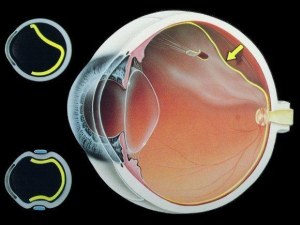

Αναφορικά με την αποκόλληση αμφιβληστροειδούς, ο αμφιβληστροειδής χιτώνας είναι ένα στρώμα νευρικού ιστού στο πίσω μέρος του ματιού που δέχεται το φως και στέλνει την εικόνα στον εγκέφαλο. Το μάτι είναι σαν μια κάμερα. Ο φακός στο μπροστινό μέρος του ματιού εστιάζει το φως πάνω στον αμφιβληστροειδή. Μπορείτε να σκεφτείτε τον αμφιβληστροειδή σαν το φίλμ της κάμερας.

Αποκόλληση αμφιβληστροειδούς συμβαίνει όταν ο αμφιβληστροειδής τραβηχθεί μακρυά από τη φυσιολογική του θέση. Ο αμφιβληστροειδής δεν δουλεύει όταν είναι αποκολλημένος. Η όραση είναι θολή, ακριβώς όπως μια φωτογραφία είναι θολή αν το φίλμ δεν είναι σε σωστή θέση μέσα στη κάμερα. Η αποκόλληση του αμφιβληστροειδούς είναι ένα σοβαρό πρόβλημα και σχεδόν πάντοτε προκαλεί τύφλωση εάν δεν αντιμετωπισθεί εγκαίρως.

Ένα καθαρό ζελέ που ονομάζεται υαλοειδές γεμίζει το εσωτερικό του ματιού μας. Με την πάροδο των ετών το υαλοειδές τραβιέται μακρυά από τον αμφιβληστροειδή που επικαλύπτει το εσωτερικό του ματιού, μια διαδικασία που καλείται αποκόλληση του υαλοειδούς. Συνήθως αυτή η αποκόλληση του υαλοειδούς ολοκληρώνεται χωρίς προβλήματα για την όραση μας. Ορισμένες φορές ωστόσο καθώς τραβιέται το υαλοειδές μπορεί να προκαλέσει ένα σχίσιμο στον αμφιβληστροειδή σε μια ή και περισσότερες περιοχές. Υγρό μπορεί να περάσει μέσα από αυτό το σχίσιμο και να ανασηκώσει τον αμφιβληστροειδή, όπως η ταπετσαρία μπορεί να ανασηκωθεί απ’τον τοίχο.

Εξωτερικό μόσχευμα σιλικόνης (scleral buckle)

Τοποθετείται μια μπάντα σιλικόνης στο εξωτερικό τοίχωμα του ματιού προκειμένου να αντιρροπήσει τις δυνάμεις που τραβούν τον αμφιβληστροειδή απ’τη θέση του. Συχνά ο χειρουργός παροχετεύει το υγρό κάτω απ’τον αποκολλημένο αμφιβληστροειδή έτσι ώστε αυτός να επιστρέψει στη φυσιολογική του θέση. Η επέμβαση πραγματοποιείται στο χειρουργείο συχνά υπό τοπική – περιοχική αναισθησία σε συνθήκες περιπατητικού χειρουργείου ημέρας.